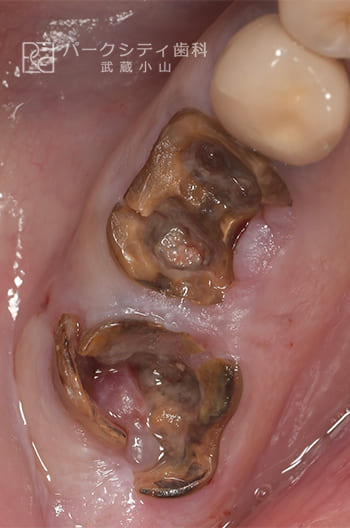

CASE.01

臼歯部を抜歯即時でインプラント治療したケース

- 主訴

- 噛めない

- 治療法

- インプラント治療

- 治療期間

- 4ヶ月

- 費用

- IP:¥275,000

増骨:¥33,000

アバットメント:¥77,000

ジルコニアクラウン:¥99,000

【リスク・副作用】

抜歯直後にインプラントを埋入するため、固定をうまくとることができない場合、また感染をおこしてしまった場合、インプラントと骨が結合しない場合があります。その場合は再手術が必要になります。